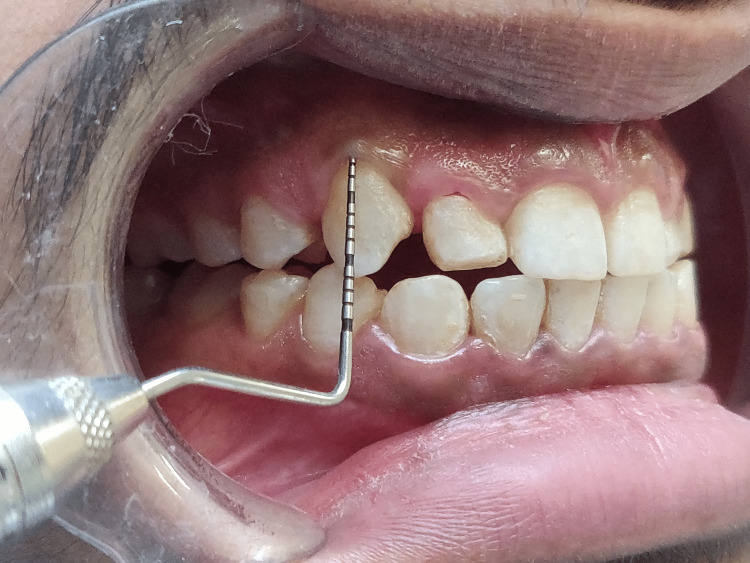

Short clinical crowns measured on the mid-buccal aspect of the height from the gingival margin to the incisal edge were found during the clinical examination to have healthy gingiva and periodontium (right central incisor - 8mm, right lateral incisors - 6mm, right canine - 7mm, left central incisor - 7mm, left lateral incisor - 5mm, left canine - 7mm) as depicted in Figures 3-8. As a result, the diagnosis of gummy grins due to altered passive eruption (type I - subgroup B) [9] was made, and it was determined to treat choice with aesthetic crown lengthening surgery with osseous reduction.

Figure 3. Clinical crown measurement of right central incisor as 8mm (11).

Figure 4. Clinical crown measurement of right lateral incisor as 6mm (12).

Figure 5. Clinical crown measurement of right canine as 7mm (13).

Figure 6. Clinical crown measurement of left central incisor as 7mm (21).

Figure 7. Clinical crown measurement of left lateral incisor as 5mm (22).

Figure 8. Marking depicting bleeding spots after pockets.